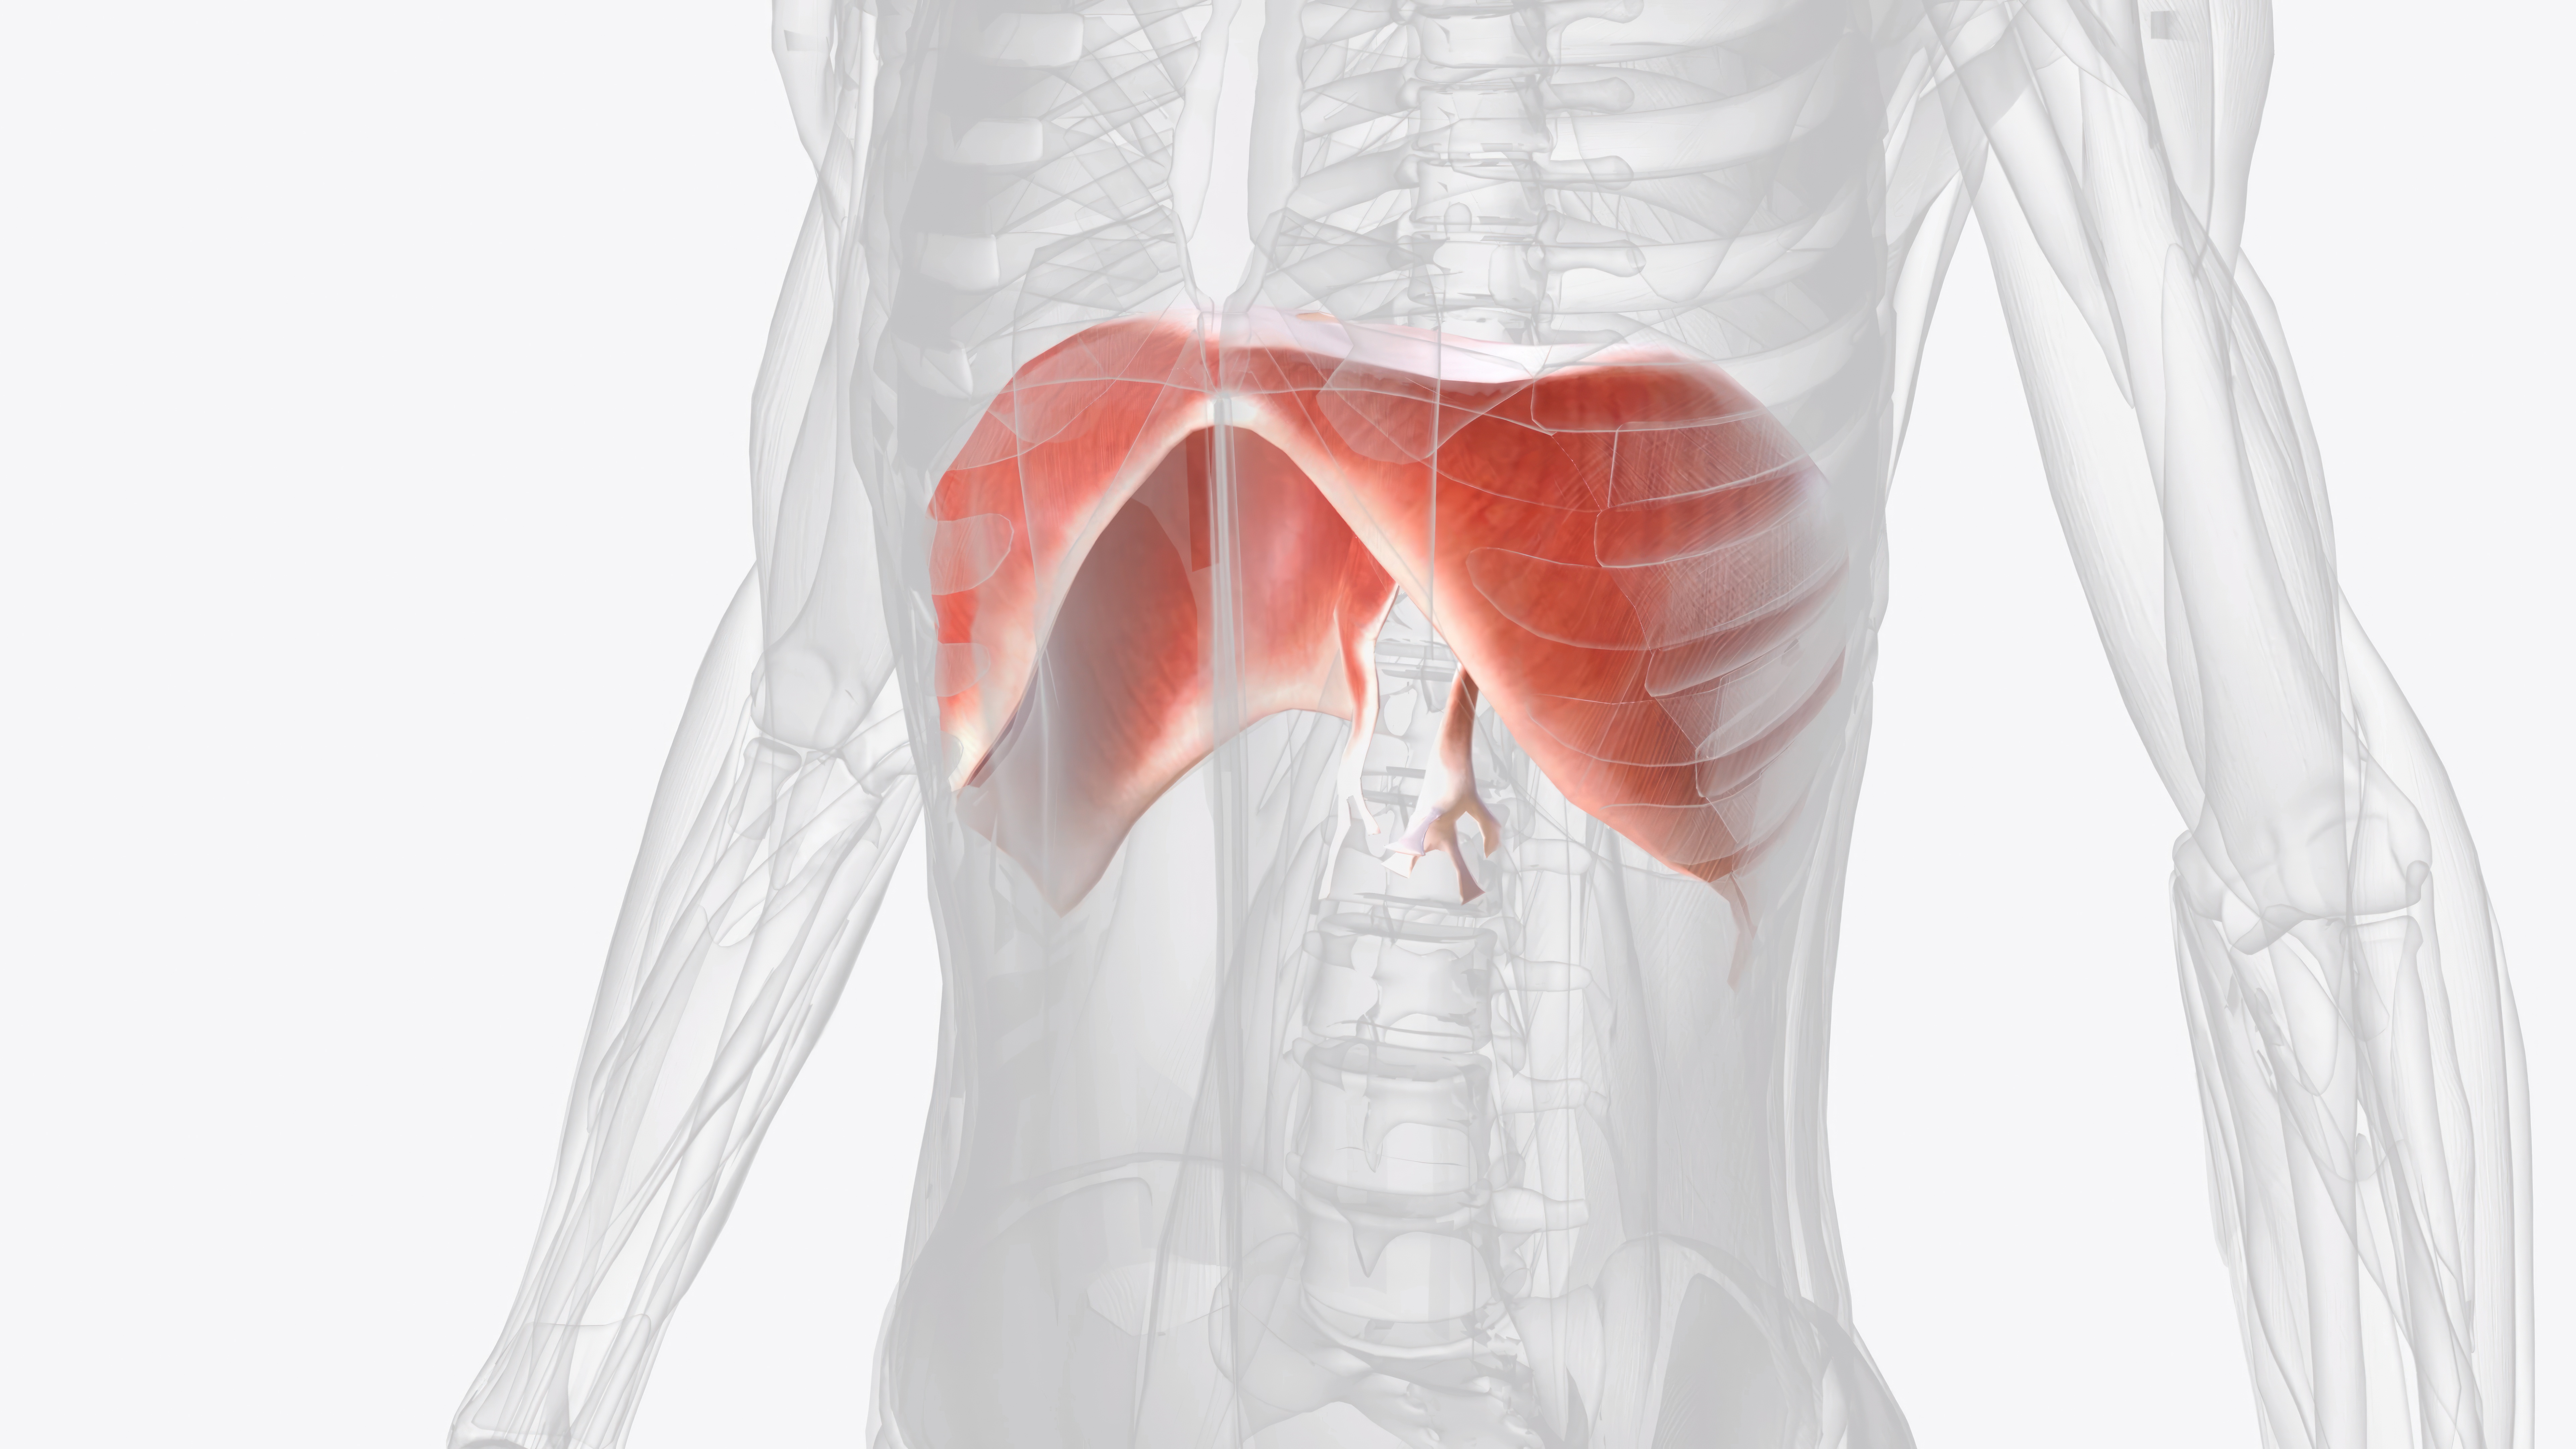

The diaphragm

The most important respiratory muscle without doubt. With hypopressives you can keep it elastic and strong. As a result, it will efficiently support not only breathing, but also the circulatory, digestive, lymphatic and nervous system.